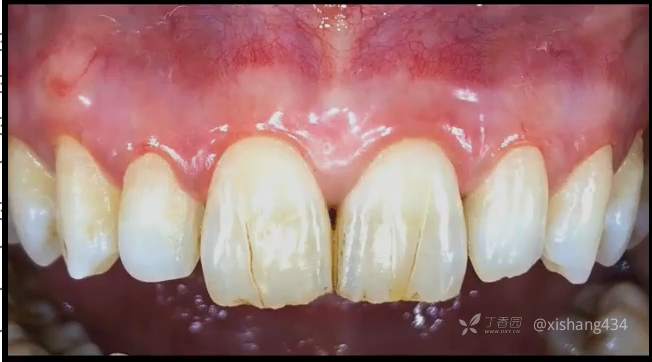

临床上有一些患者牙龈黑色素沉着,传统的方法脱色有手术刀,金钢砂车针磨除,操作均不方便。采用激光脱色,操作简便,效果也不错。